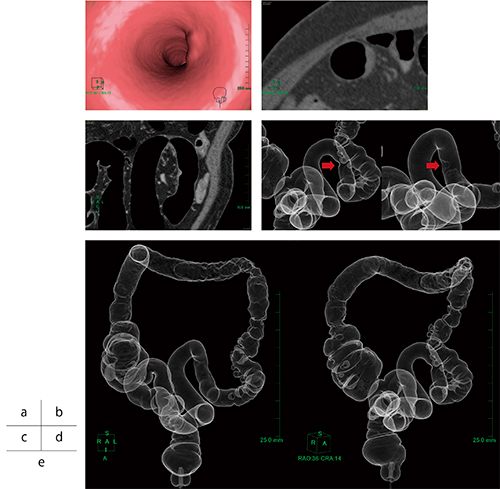

解析では,はじめに仰臥位,腹臥位の2つのボリュームデータを大腸解析ソフトウェアで開き,経路が正しく取られていることを確認する。前処置不良でなければほぼ経路に修正は要らないが,一部腸管壁に接する所があれば経路点を増やしたり,動かしたりすることで簡単に修正はできる(図1)。

図1 経路探索画面

次に,仮想内視鏡モードで観察していく。比較読影モードであれば,仰臥位,腹臥位ともほぼ同じ位置で表示されるので比較しやすい。片方の体位で病変らしきものがある場合に,もう片体位で移動していれば残渣と考え,同じ位置にあれば病変が疑われる(図2)。

図2 比較読影モード

仰臥位(a),腹臥位(b)とも同じ位置に隆起性病変が見られ,残渣ではない(CT値40HU)。

ポリープなど病変が疑われる場合は,ポリープ観察ツールで病変の直交断面を2D画像ですぐに見ることができ,計側にも大変便利である(図3)。

図3 ポリープ(直腸カルチノイド)の計測

a:仮想内視鏡画像でのポリープ観察ツール使用時

b:ポリープ観察ツールでの直交断面画像(大きさ10.2mm,CT値44HU)

c:同部位の内視鏡画像

前医にて便潜血陽性で大腸内視鏡検査が行われ,右結腸から下行結腸にかけての炎症性所見とS状結腸に隆起性病変が認められ,腺癌と診断され当院に紹介となった。

当院の大腸内視鏡検査では痛みが強く,下行結腸途中までの検査になってしまったが,S状結腸にType2の進行がんを思わせる隆起性病変(図5)が認められ,下行結腸途中から全周性の発赤で易出血性であった。大腸内視鏡検査より潰瘍性大腸炎を発生母地としたcolitic cancerを疑い,下行結腸から口側の大腸と血管分岐の情報を得るためにCT angiographyを含めた大腸CT検査が行われた。

図5 大腸内視鏡画像

大腸CT検査では,上行結腸から下行結腸途中にかけての粗造な粘膜変化と壁の肥厚,S状結腸に中心陥凹の隆起性病変が認められた。粘膜の変化は上行結腸途中まで見られ,盲腸部は正常と思われた。また,隆起性病変付近のS状結腸は,潰瘍性大腸炎の特徴の一つであるハウストラの消失(鉛管像)が見られた(図6)。

図6 Colitic cancerが疑われた患者の大腸CT検査

a:仮想内視鏡画像 b:アキシャル画像 c:コロナル画像

d:仮想注腸画像(→隆起性病変) e:仮想注腸画像(腹臥位)。

隆起性病変付近の鉛管像と,上行結腸から下行結腸の粘膜変化が見られる。